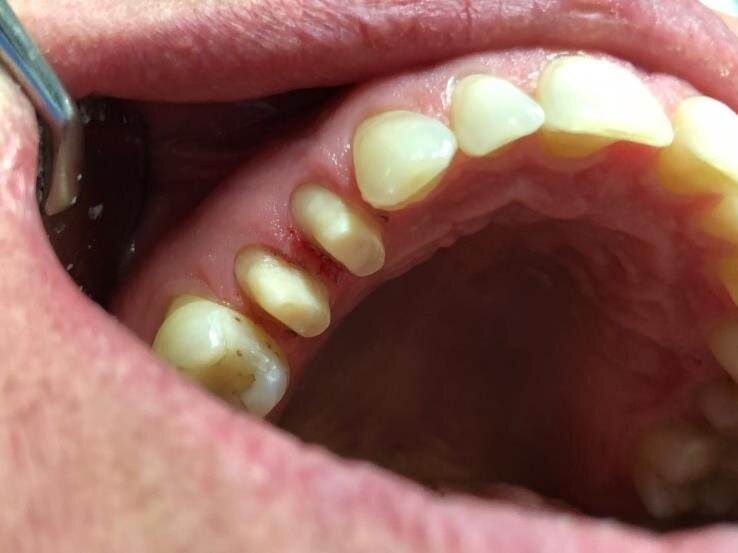

A 52-year-old woman came to my practice due to acute pain in the region of the first quadrant. After a careful, intraoral and radiographic objective examination, we diagnosed destructive caries of teeth 14 and 15.

In the first instance, we performed root canal treatment of the teeth and consequently reconstructed both of them with Fiberglass Posts and covered them with ceramics manufactured with FONA MyCrown CAD/CAM system.

Fig. 1: Teeth preparation